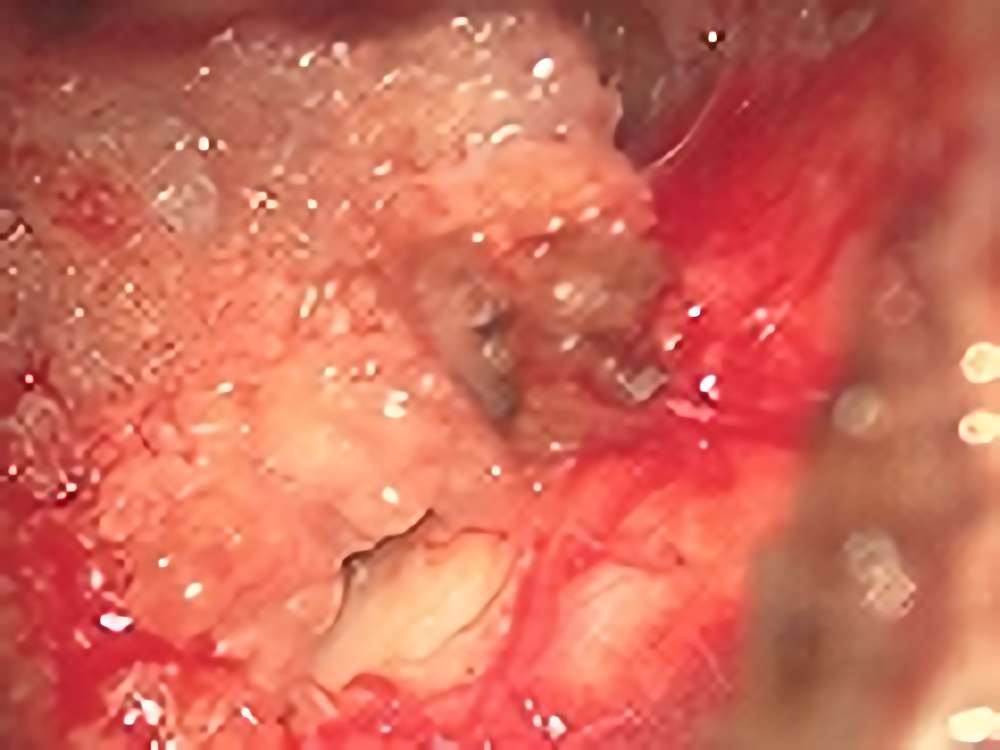

'13年12月

50代

転移性脳腫瘍

No.’13_191 手術前1

No.’13_191 摘出 前

No.’13_191 摘出 後